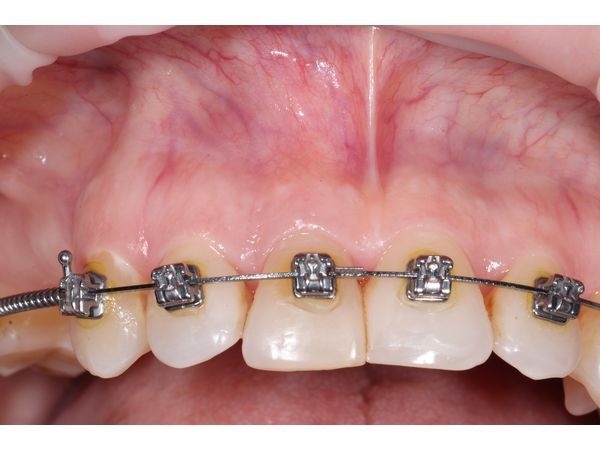

При внешнем осмотре лицо симметрично, кожа нормального цвета. В полости рта переходная складка возле корня зуба 1.1 покраснела и слегка отекла. При прощупывании ощущалась возвышенность. Надавливание вызывало боль.

- выполнили полулунный разрез по подвижной слизистой в области двух верхних центральных резцов (1.1 и 1.2);